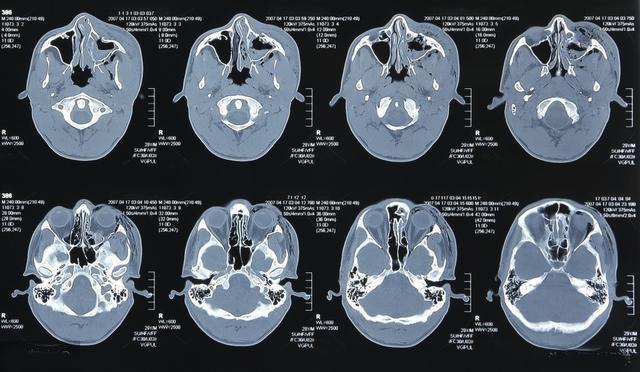

很多人不舒服到医院来检查,会问是不是核磁共振检查得最清楚,甚至会想当然的认为做了磁共振会把身体所有的部位都扫描到,就像探测仪一样,全身扫一下就知道毛病在哪儿了。磁共振可以检查全身部位吗?可以的,头部、颈部、胸部、腹部以及脊柱四肢都可以使用磁共振检查,但是磁共振检查非常耗时,一个部位就要一二十分钟,如果所有部位都做的话,加上摆位时间,估计得耗费一天时间,而且有些部位还不一定有CT清楚。磁共振检查过程中,不同的序列出现不同的声音,在一个狭小密闭黑暗空间躺一天,不可以动,而且呼吸运动还得配合技师,这个难度是相当大的,有幽闭症的人更不可能完成。

磁共振并不是检查神器,在某些方面它很有优势,在骨、关节与软组织病变的诊断方面,磁共振成像具有多于CT数倍的成像参数和高度的软组织分辨率,其对软组织的对比度明显高于CT,能够更有效、更早的发现病变。它可不用血管造影剂,即显示血管的结构,故对血管、肿块、淋巴结和血管结构之间的相互鉴别,有其独到之处。磁共振能显示心腔、心肌、心包及心内其它细小结构,是诊断各种心脏病以及心功能检查的可靠方法。对于胆道梗阻的病人,如果体质弱,无法行经皮肝穿胆道造影(PTC)和内窥镜逆行胰胆管造影(ERCP)的患者,可以选择MRCP(磁共振胆胰管成像),直接观察到胆道管腔内外病变情况,并根据病变部位、形态进行病因的判断,定性诊断准确率达64%~98%。

但是由于磁共振检查耗时长,会受到运动干扰,病人自主或不自主的活动可引起运动伪影,影响诊断,尤其是胸部及腹部MRI,因此对于肺部炎症、肺部肿瘤、腹部肝胆脾胰及淋巴结等实质性脏器行CT检查更合适。另外磁共振不适用于危重病人和急诊病人。核磁共振的层厚较CT厚,一些微小的病变存在漏诊风险。磁共振对于空腔器官及运动的器官,比如食管、胃肠道、肺部并不能很好的显影。除此之外,体内有金属及有心脏起搏器的人不可以做核磁共振检查。